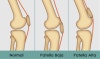

슬개고위증(Patella alta)와 슬개하위증(Patella baja)2016-10-09카테고리 106원본 보기 * 슬개고위증(Patella alta) : 선천적 변이나 슬개골 힘줄의 파열 * 슬개하위증(Patella baja) : 선천적 변이나 대퇴사두근건의 파열 ← 이전 글Knee Axial view에서의 Measurements다음 글 →Knee X-ray의 Anatomy와 Positioning같은 카테고리 글2017-06-10톰슨 검사(Thompson test) : 아킬레스건 파열을 조사하는 테스트2017-06-09Apley 압박 검사(Apley compression test) : 반월상 연골 손상을 조사하는 테스트2017-06-08맥머레이 시험(McMurray test) : 반월상 연골 손상을 조사하는 테스트← 전체 글로 돌아가기